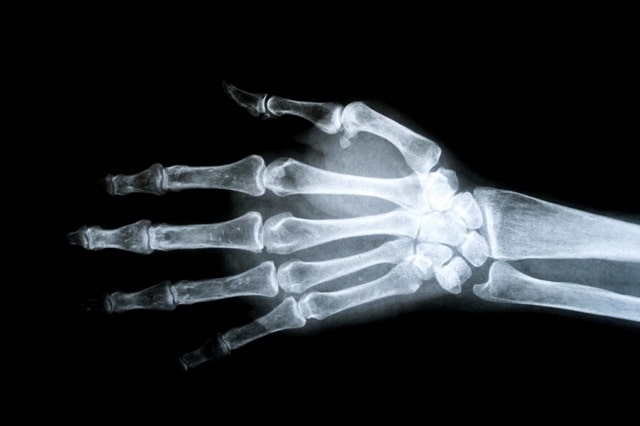

- 손 골관절염: 국소부위 통증이므로 대부분 혈액검사상 염증수치 정상, x-ray 상 관절강 좁아짐과 골극형성

- 류마티스 관절염: 혈액검사상 염증수치 상승, 류마티스 관련인자 (anti CCP, rheumatoid factor)양성, x-ray 상 관절 미란(침식)